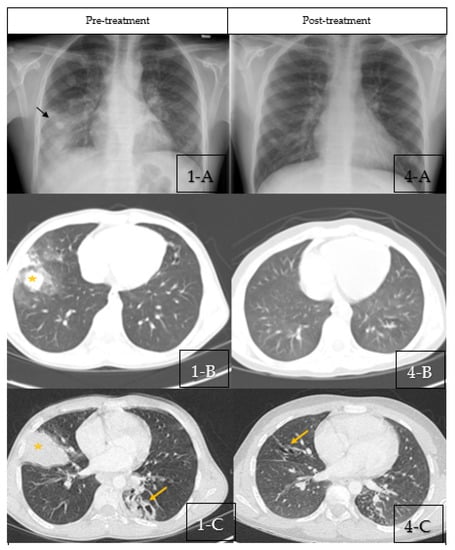

Figure 1.

(1-A–1-C) Pre-treatment Imaging. (1-A): Chest X-ray pre-treatment with pulse steroids showing right middle lobe con-solidation (Black Arrow) with bilateral scattered nodular opacities. (1-B,1-C): Coronal sections of chest CT scan at diagnosis showing bilateral central bronchiectasis, mucus impaction (Yellow Arrow) and areas of segmental, and subsegmental atelectasis (Star). (4-A–4-C) Post-treatment Imaging: (4-A): Chest X-ray post-treatment with pulse steroids showing disappearance of right middle lobe consolidation. (4-B,4-C): Coronal sections of chest CT scan post-treatment with pulse steroids showing resolution of the previous findings with residual bronchiectasis (Yellow arrows).